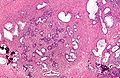

Benign prostate hyperplasia

Both the glandular epithelial cells and the stromal cells (including muscular fibers) undergo hyperplasia in BPH.[2] Most sources agree that of the two tissues, stromal hyperplasia predominates, but the exact ratio of the two is unclear.[39]:694

Anatomically the median and lateral lobes are usually enlarged, due to their highly glandular composition. The anterior lobe has little in the way of glandular tissue and is seldom enlarged. (Carcinoma of the prostate typically occurs in the posterior lobe – hence the ability to discern an irregular outline per rectal examination). The earliest microscopic signs of BPH usually begin between the age of 30 and 50 years old in the PUG, which is posterior to the proximal urethra.[39]:694 In BPH, the majority of growth occurs in the transition zone (TZ) of the prostate.[39]:694 In addition to these two classic areas, the peripheral zone (PZ) is also involved to a lesser extent.[39]:695 Prostatic cancer typically occurs in the PZ. However, BPH nodules, usually from the TZ are often biopsied anyway to rule out cancer in the TZ.[39]:695 BPH can be a progressive growth that in rare instances leads to exceptional enlargement.[40] In some males, the prostate enlargement exceeds 200 to 500 grams.[40] This condition has been defined as giant prostatic hyperplasia (GPH).[40]